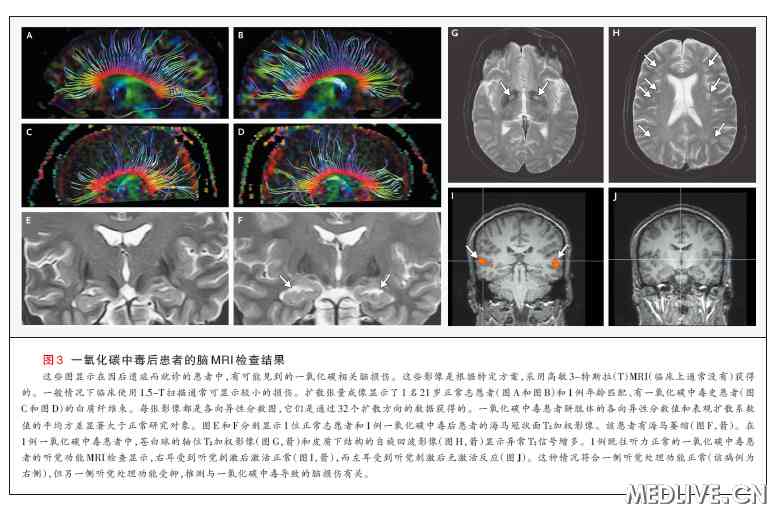

患者一氧化碳中毒后的脑磁共振成像(MRI)检查(为了研究目的而实施,某些病例有施行MRI的临床适应证,例如为了除外与一氧化碳暴露无关的疾病),有可能显示异常结果(图3)。在一项纳入一氧化碳中毒患者的前瞻性研究中,脑MRI显示(患者的)T2加权高信号数,多于基准数据库中的高信号数 21。虽然影像学异常改变的发生率还不知道,但其他纳入一氧化碳中毒患者的研究曾经报告过中毒数年后的基底神经节病变22、海马和其他结构萎缩23,以及中毒1个月后扩散张量成像的异常结果25。然而,这些异常对一氧化碳中毒而言都不具有特异性。